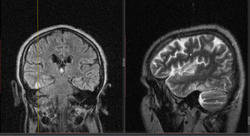

Мужчина 1964 г.р. Жалобы на нарушение памяти, снижение зрения и кратковременную потерю сознания, температура нормальная.

Я думаю что это может быть какой нибудь васкулит, либо Posterior Reversible Encephalopathy Syndrome, о чем можно думать в данном случае?

eto pres

Я представлял синдром с более выраженным изменением сигнала от белого вещества и меньшим - коры.